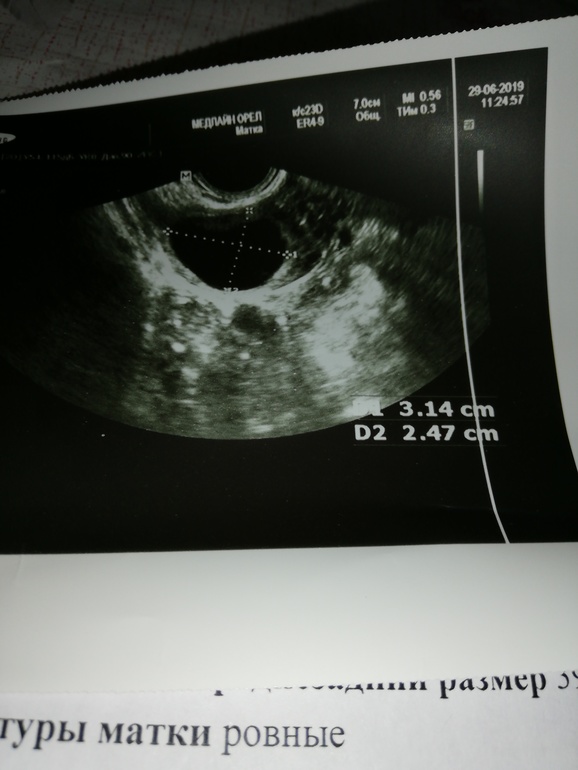

Здравствуйте девочки, это скорее крик о помощи, я просто уже не знаю что делать. Я знаю, что у кого то есть проблемы и по серьёзнее, чем моё непонятное нытье. В сентябре прошлого года была киста желтого тела, и беременность как потом выяснилось, но было прерывание. Затем кок на пол года. Сейчас первый цикл отмены, начала тестить овуляцию, где то 14,15 день увидела 2 яркие, были выделения Яб, грудь болела, тянущие боли с отдачей в задний проход, думала все, вот она. Пошла на узи 19д,сказала да, овуляция жт 23мм.я успокоилась, но начало тянуть с права, думаю дай схожу, 23 дц, и тут на тебе, то ли кжт, то ли фолликулярная. Я прикрепляю снимки. Может быть кто нибудь сталкивался с похожим, или может кто нибудь знает что именно у меня

Так я сегодня на узи спрашиваю, какая киста, она мне фолликулярная, овуляции у вас не было. А предыдущая, сказала да была.

По фото похоже на фолликул. У меня был в августе фолликул 33*21 мм, узистка сказала киста, но я через день пришла снова на УЗИ и там было ЖТ. По фото фолликул и ЖТ отличаются, у ЖТ ободок видно с неровными краями.

Вот ЖТ

А это фолликул

Ваши снимки не о чем не скажут даже врачу. На УЗИ что ЖТ что фолмкулярная киста совершенно одинаковые. Единственное как их можно отличить это наблюдать за фолликулов с 2-5 дня цикла.

А сейчас можно только гадать